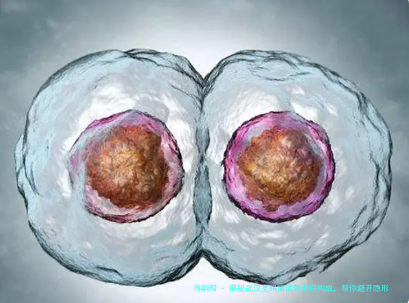

当病人获得多个优质胚胎儿时期,可将余下胚胎冷冻保存,以便后续移植使用。这不但提高了单次取卵的成功率,也是为患者免去了重复促排卵的费用和时间。